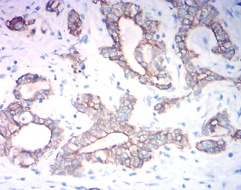

KRT19 Mouse Monoclonal antibody[2A1G9]

IHC    1/200 - 1/1000